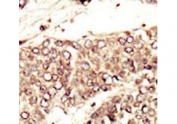

IHC testing of FFPE human cancer tissue with IGF1 Receptor antibody. HIER: steam section in pH6 citrate buffer for 20 min and allow to cool prior to staining.

Applications Immunohistochemistry (FFPE) : 1:50-1:100